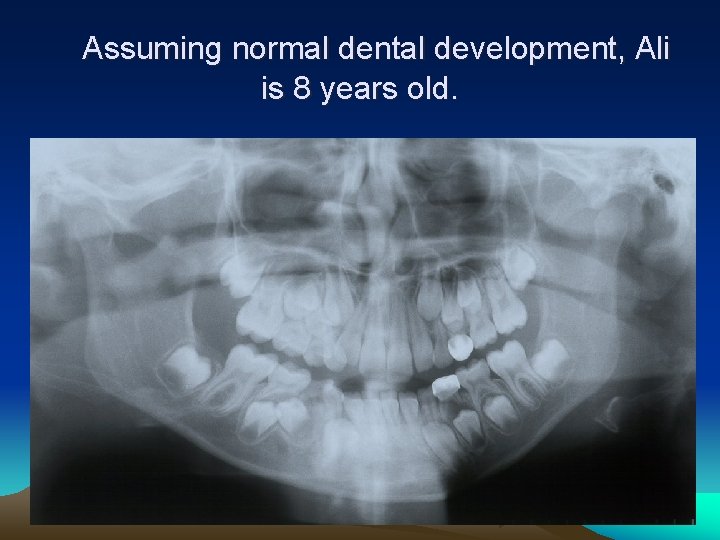

How old is Ali assuming normal dental development?

Assuming normal dental development, Ali is 8 years old.